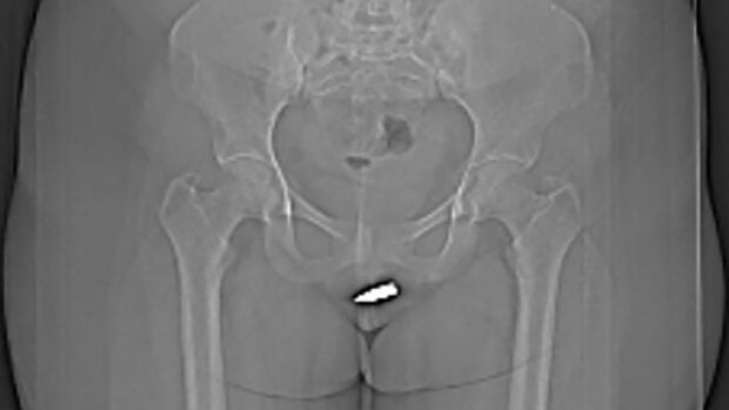

24-річну сомалійку доставили до лікарні Ердогана в Могадішо з сильним болем після того, як 2-сантиметрова куля вразила її, коли вона сиділа у вітальні.

Комп’ютерна томографія показала, що куля застрягла в кліторі і безпечно видалити її можна було лише хірургічним шляхом.

Опублікувавши рентгенівські знімки незвичного поранення і етапи самої операції в журналі International Journal of Surgery Case Reports, лікарі заявили, що, на їхню думку, цей випадок є першим і унікальним, оскільки куля не продовжила свій шлях у тілі, а залишилася в кліторі, пише науковє видання ScienceDirect.

Під місцевою анестезією кулю видалили. Вже наступного дня жінку виписали додому у задовільному стані. Контрольний огляд через місяць показав, що жодних ускладнень не виникло.